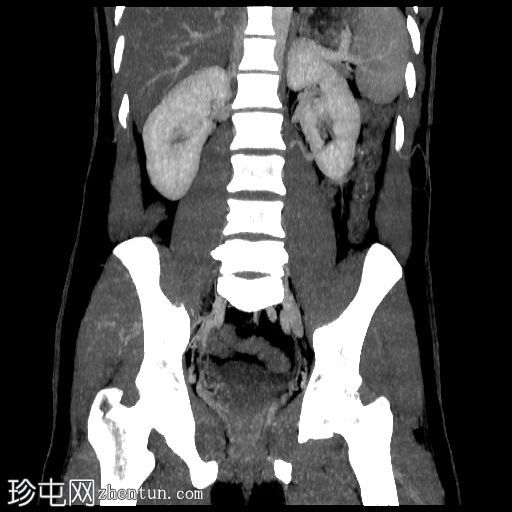

冠状位

血管窗

CT肾血管造影显示一条起源于左肾下段的副肾静脉,该静脉环绕主动脉走行,并接受来自腰静脉的属支,走行于主动脉后方,最终汇入下腔静脉。

双侧肾脏集合系统重复,分为上极和下极两部分。右侧输尿管在中段汇合,而左侧输尿管在进入膀胱前仍部分分离,符合双侧部分输尿管重复畸形(双分输尿管)。

左肾下极可见一大小约7毫米的皮质性囊肿。

胃脾区可见一小型副脾。

本病例展示了一条环绕主动脉的副左肾静脉,其走行于主动脉后方并汇入下腔静脉,而右肾静脉解剖结构正常。

双侧肾动脉解剖结构正常,双侧肾动脉均起源于L2椎体水平的腹主动脉,管径正常,无狭窄、动脉瘤、夹层或副动脉。

双侧重复肾盂输尿管系统,上下极部分明显。右侧重复的输尿管在中段汇合,而左侧输尿管在进入膀胱前仍部分分离,符合双侧部分输尿管重复畸形(双分输尿管)。双肾大小、位置、轮廓和实质厚度均正常,造影剂浓度和排泄功能正常。未见肾结石、肾积水或局灶性肾脏病变。

左肾下极可见约7 mm的Bosniak I型单纯性皮质肾囊肿。

其他偶然发现包括II级肝脂肪变性、胃脾区可见一小副脾、双侧L5椎弓崩裂伴L5相对于S1的I级滑脱。